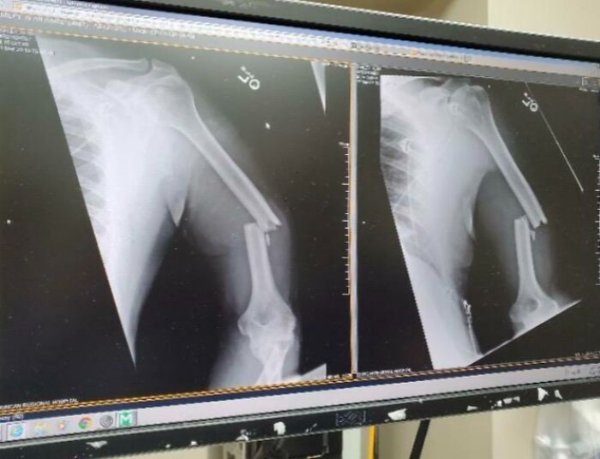

Fascinating Medical Photos